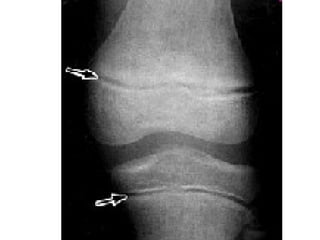

[~Begins Week 27-29]

• Center (both inner and outer) of bone model

continues to ossify.

• Ends remain as cartilage, continue to undergo

mitosis  Elongation.

• Ossification was “chasing” Cartilage

Formation to the ends of the bone.

• Epiphyses ossify…. Cartilage remains on

outer surface of epiphyses and at Epiphyseal

Plate.